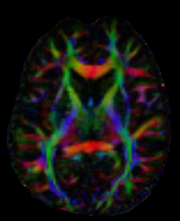

As an exercise, you can try to calculate color FA with your datasets. You will need to replace the filepaths fdwi, fbval and fbvec. Here is what a slice should look like.

../_images/colorfa.png